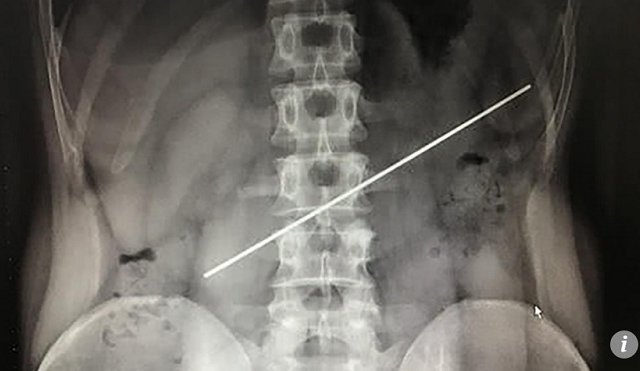

TQ: Nuốt thanh thép dài 20cm nhận 800 USD, lấy ra tốn gấp 4 lần

Một người đàn ông nuốt thanh thép dài 20cm sau để nhận 800 USD, nhưng một năm sau phải tốn gấp 4 lần số tiền...